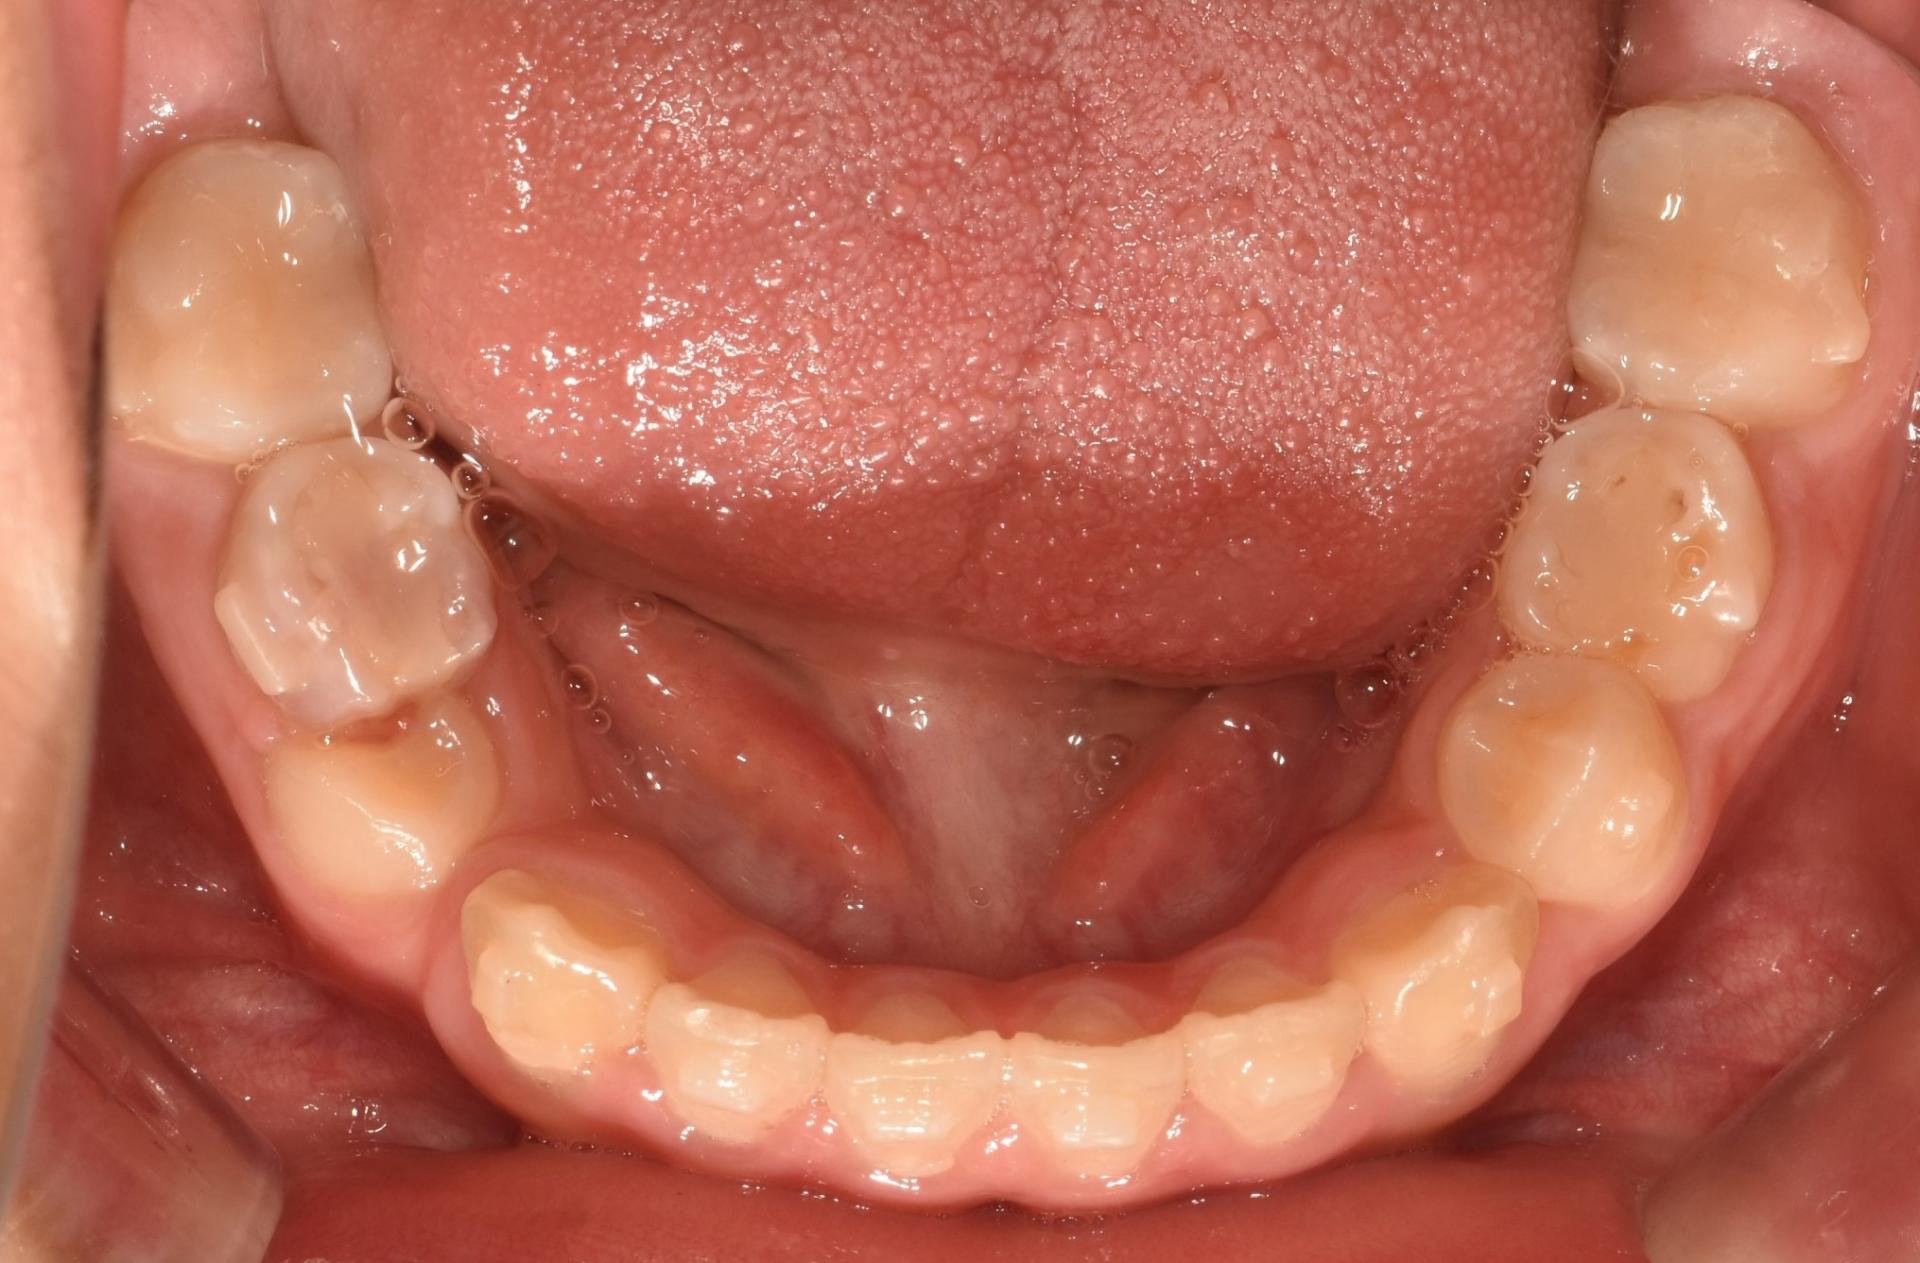

치료 전 구강 내 사진입니다 .

앞니가 벌어져 있고, 치아가 나올 공간이 부족합니다. 앞니끼리 서로 부딪히고 있네요.